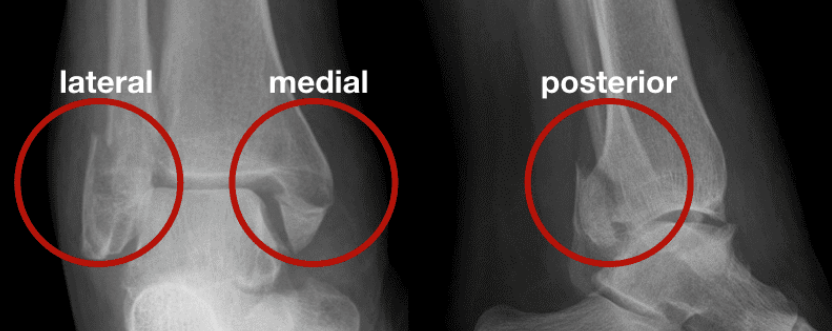

三踝包括:内踝:胫骨远端;外踝:腓骨远端;后踝:又叫后唇,是胫骨和距骨关节面的后缘。

三踝骨折:内踝、外踝和后踝同时发生不同程度的骨折或韧带损伤,是踝关节损伤中最严重的类型之一。它将严重影响踝关节的负重以及稳定功能。